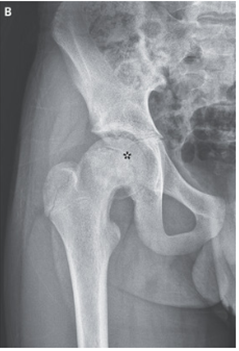

骨盤X-p施行。右大腿骨骨端の後方変異が示され、「コーンから落ちたアイスクリーム」と表現される所見だった(星印)。

上記所見より「大腿骨頭骨端すべり症」と診断された。

大腿骨近位部が前外側および上方に偏位するため、骨端が後方および下方に偏位したように見えるのが特徴。